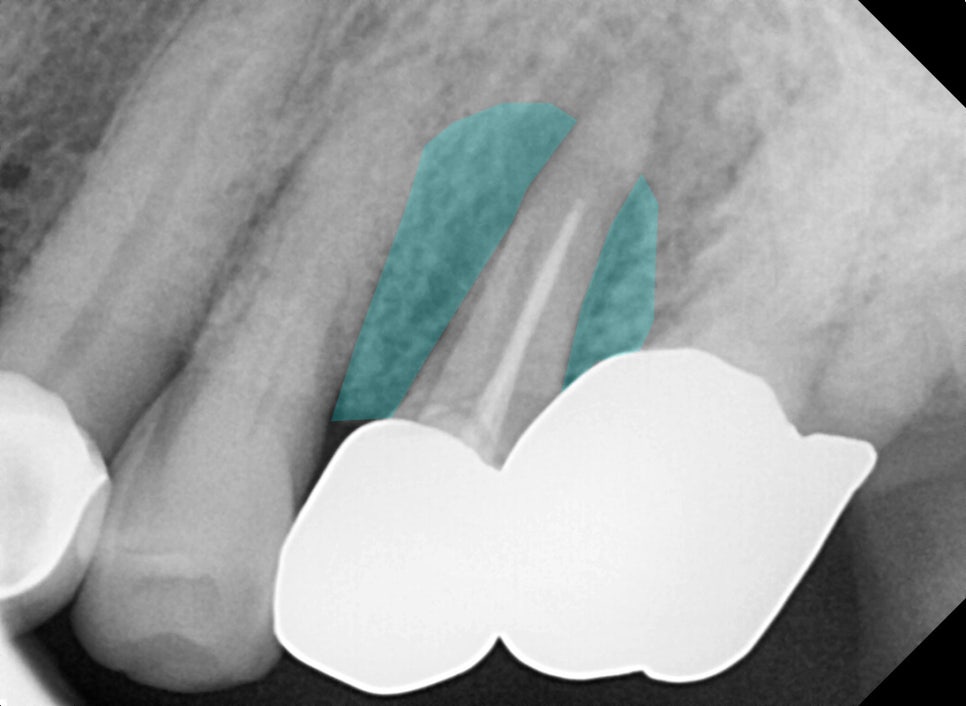

서울바르디치과에 준비되어 있는

디지털 장비를 활용해

방사선 사진을 찍어 보았습니다.

왼쪽 위 작은 어금니 주변으로

거뭇한 뿌리 끝 염증이

확인되는데요.

예전에 신경 치료했던

치아 속으로 탈이 난

모습입니다.

근단부 끝까지

제거 및 충전이

되지 않아 보여

재신경치료(re-endo)를

시도해 볼 수도 있겠지만,

심한 병소로 주변 뼈가

많이 녹아 있는 모습에

자연 치아를 살리기는

무리가 있어 보입니다.